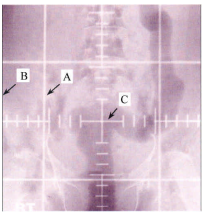

53. 附圖為一張典型傳統模擬攝影機所拍攝的放射治療模擬攝影片,其中 B 所代表的攝影範圍大小是由 下列何者來決定的?

(A) fiducial plates (B) primary collimator (C) shutters/blades (D) field defining wires